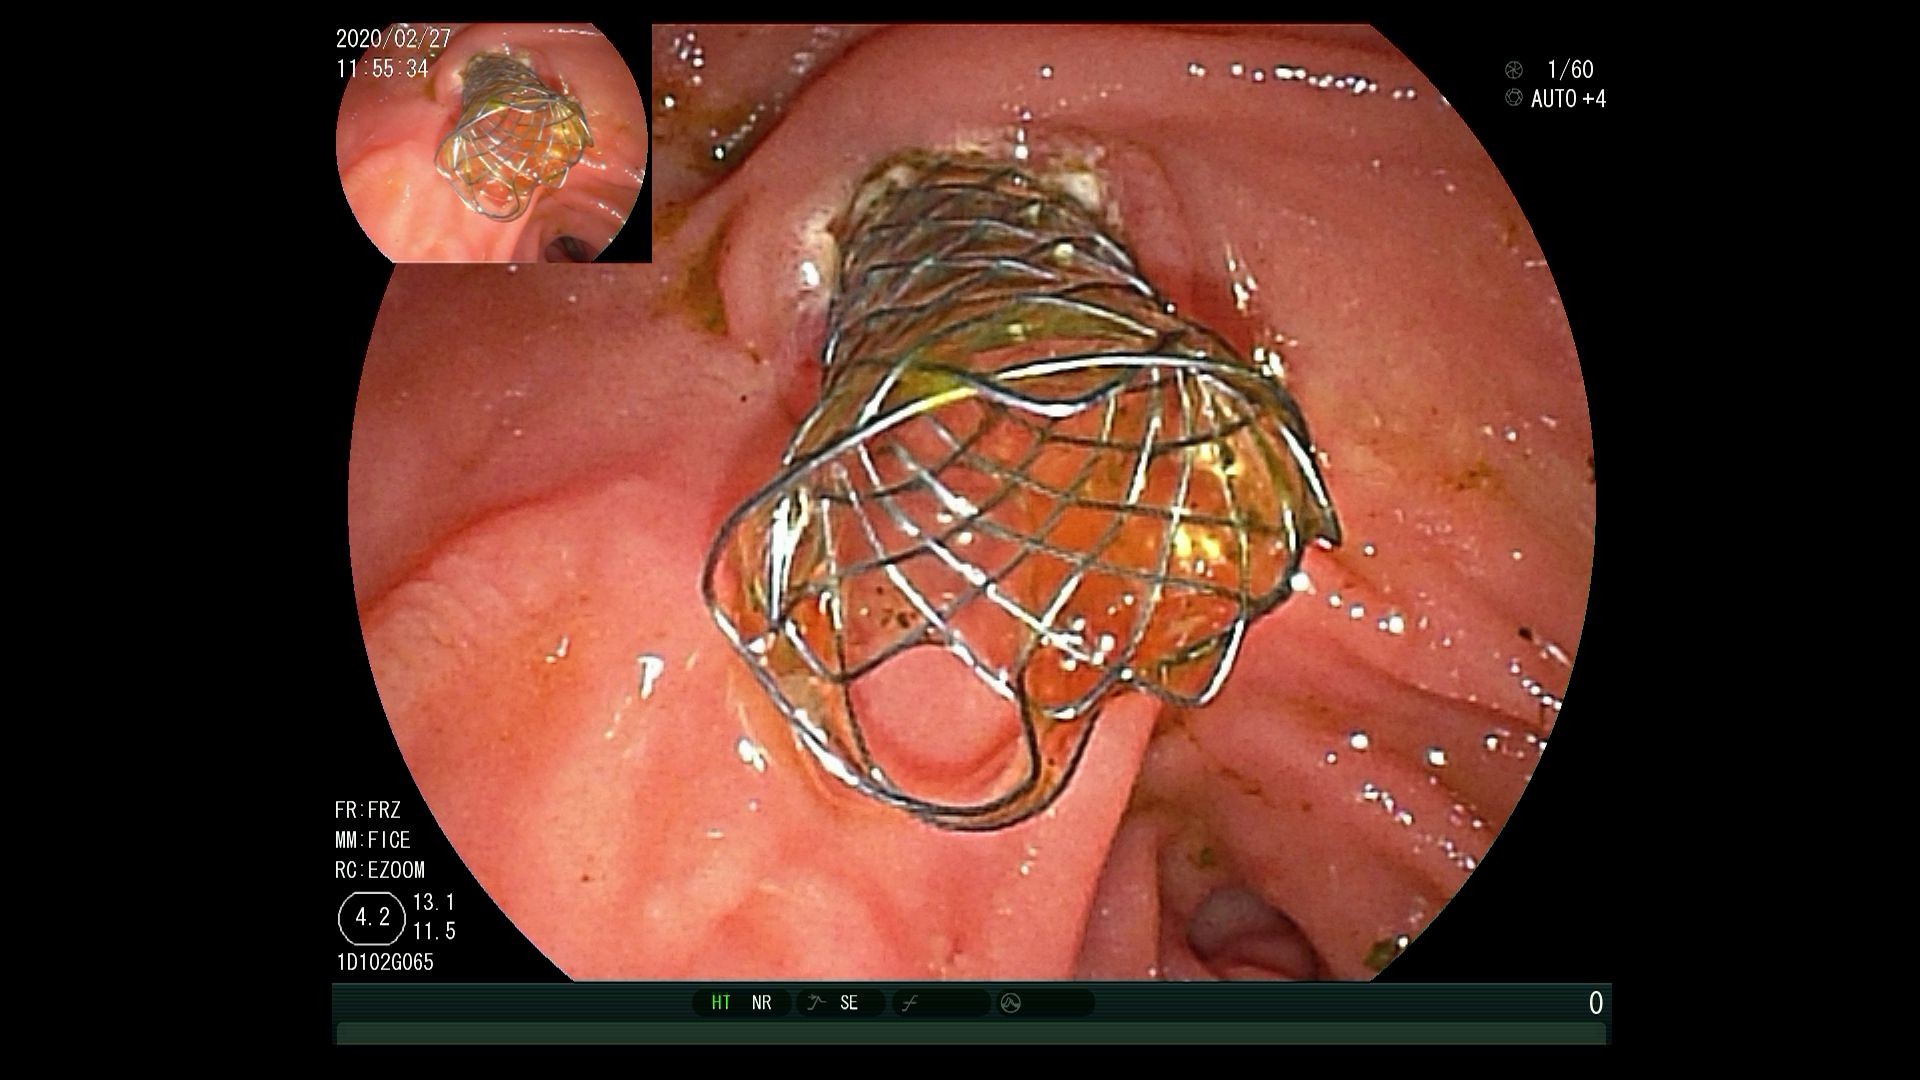

对于高龄患者,或已经有转移的,无法进行手术治疗的患者,经内镜逆行胰胆管造影术(ERCP)放置胆道支架,解除胆道梗阻,减黄治疗是主要的方法,可明显延长生存期,提高生活质量,均优于外科手术。同时也可以手术中放置胰管支架,对胰腺癌后期疼痛缓解有非常明显的作用。

支架可以放置金属支架或塑料支架,可以快速减黄,提高生活质量、延长生存期。

(图1:造影下放置胆总管金属支架。图2:内镜下放置胆总管金属支架。图3:同时放置胆道塑料支架和胰管支架。图4:放置金属支架同时放置放射粒子支架局部放疗)